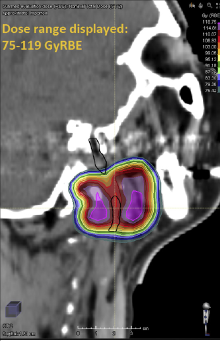

I sitt PhD prosjekt har overlege Jon Espen Dale analysert relasjonen mellom doser til normalt vev og bivirkninger hos pasienter som er behandlet med karbonjoner  ved Centro Nazionale di Adroterapia Oncologica, CNAO, Pavia, Italy og National Institute for Radiological Sciences, Tokyo, Japan. Han har hatt lengre utenlandsopphold i Italia.

Prosjekt 1

I prosjektet analyseres i detalj dose fra proton eller karbonstråling ved rebestråling etter tidligere fotonstråling has pasienter som får tilbakefall i det tidligere bestrålte området. Hovedpulsåren til hjernen, carotis arterien, er den mest følsomme strukturen i dette området og ved skade av karveggen kan veggen sprekke og pasienten dø av styrtblødning («carotid blowout»).

Risikoen for carotid blowout var 2,7%, lik tidligere studier med fotoner. Vi kan altså oppnå bedre kreftkontroll med partikkelstråling uten å øke sjansen for skade av hovedpulsåren.  Artikkel: Dale JE et al. Adv Radiat Oncol 2:465-74, 2017